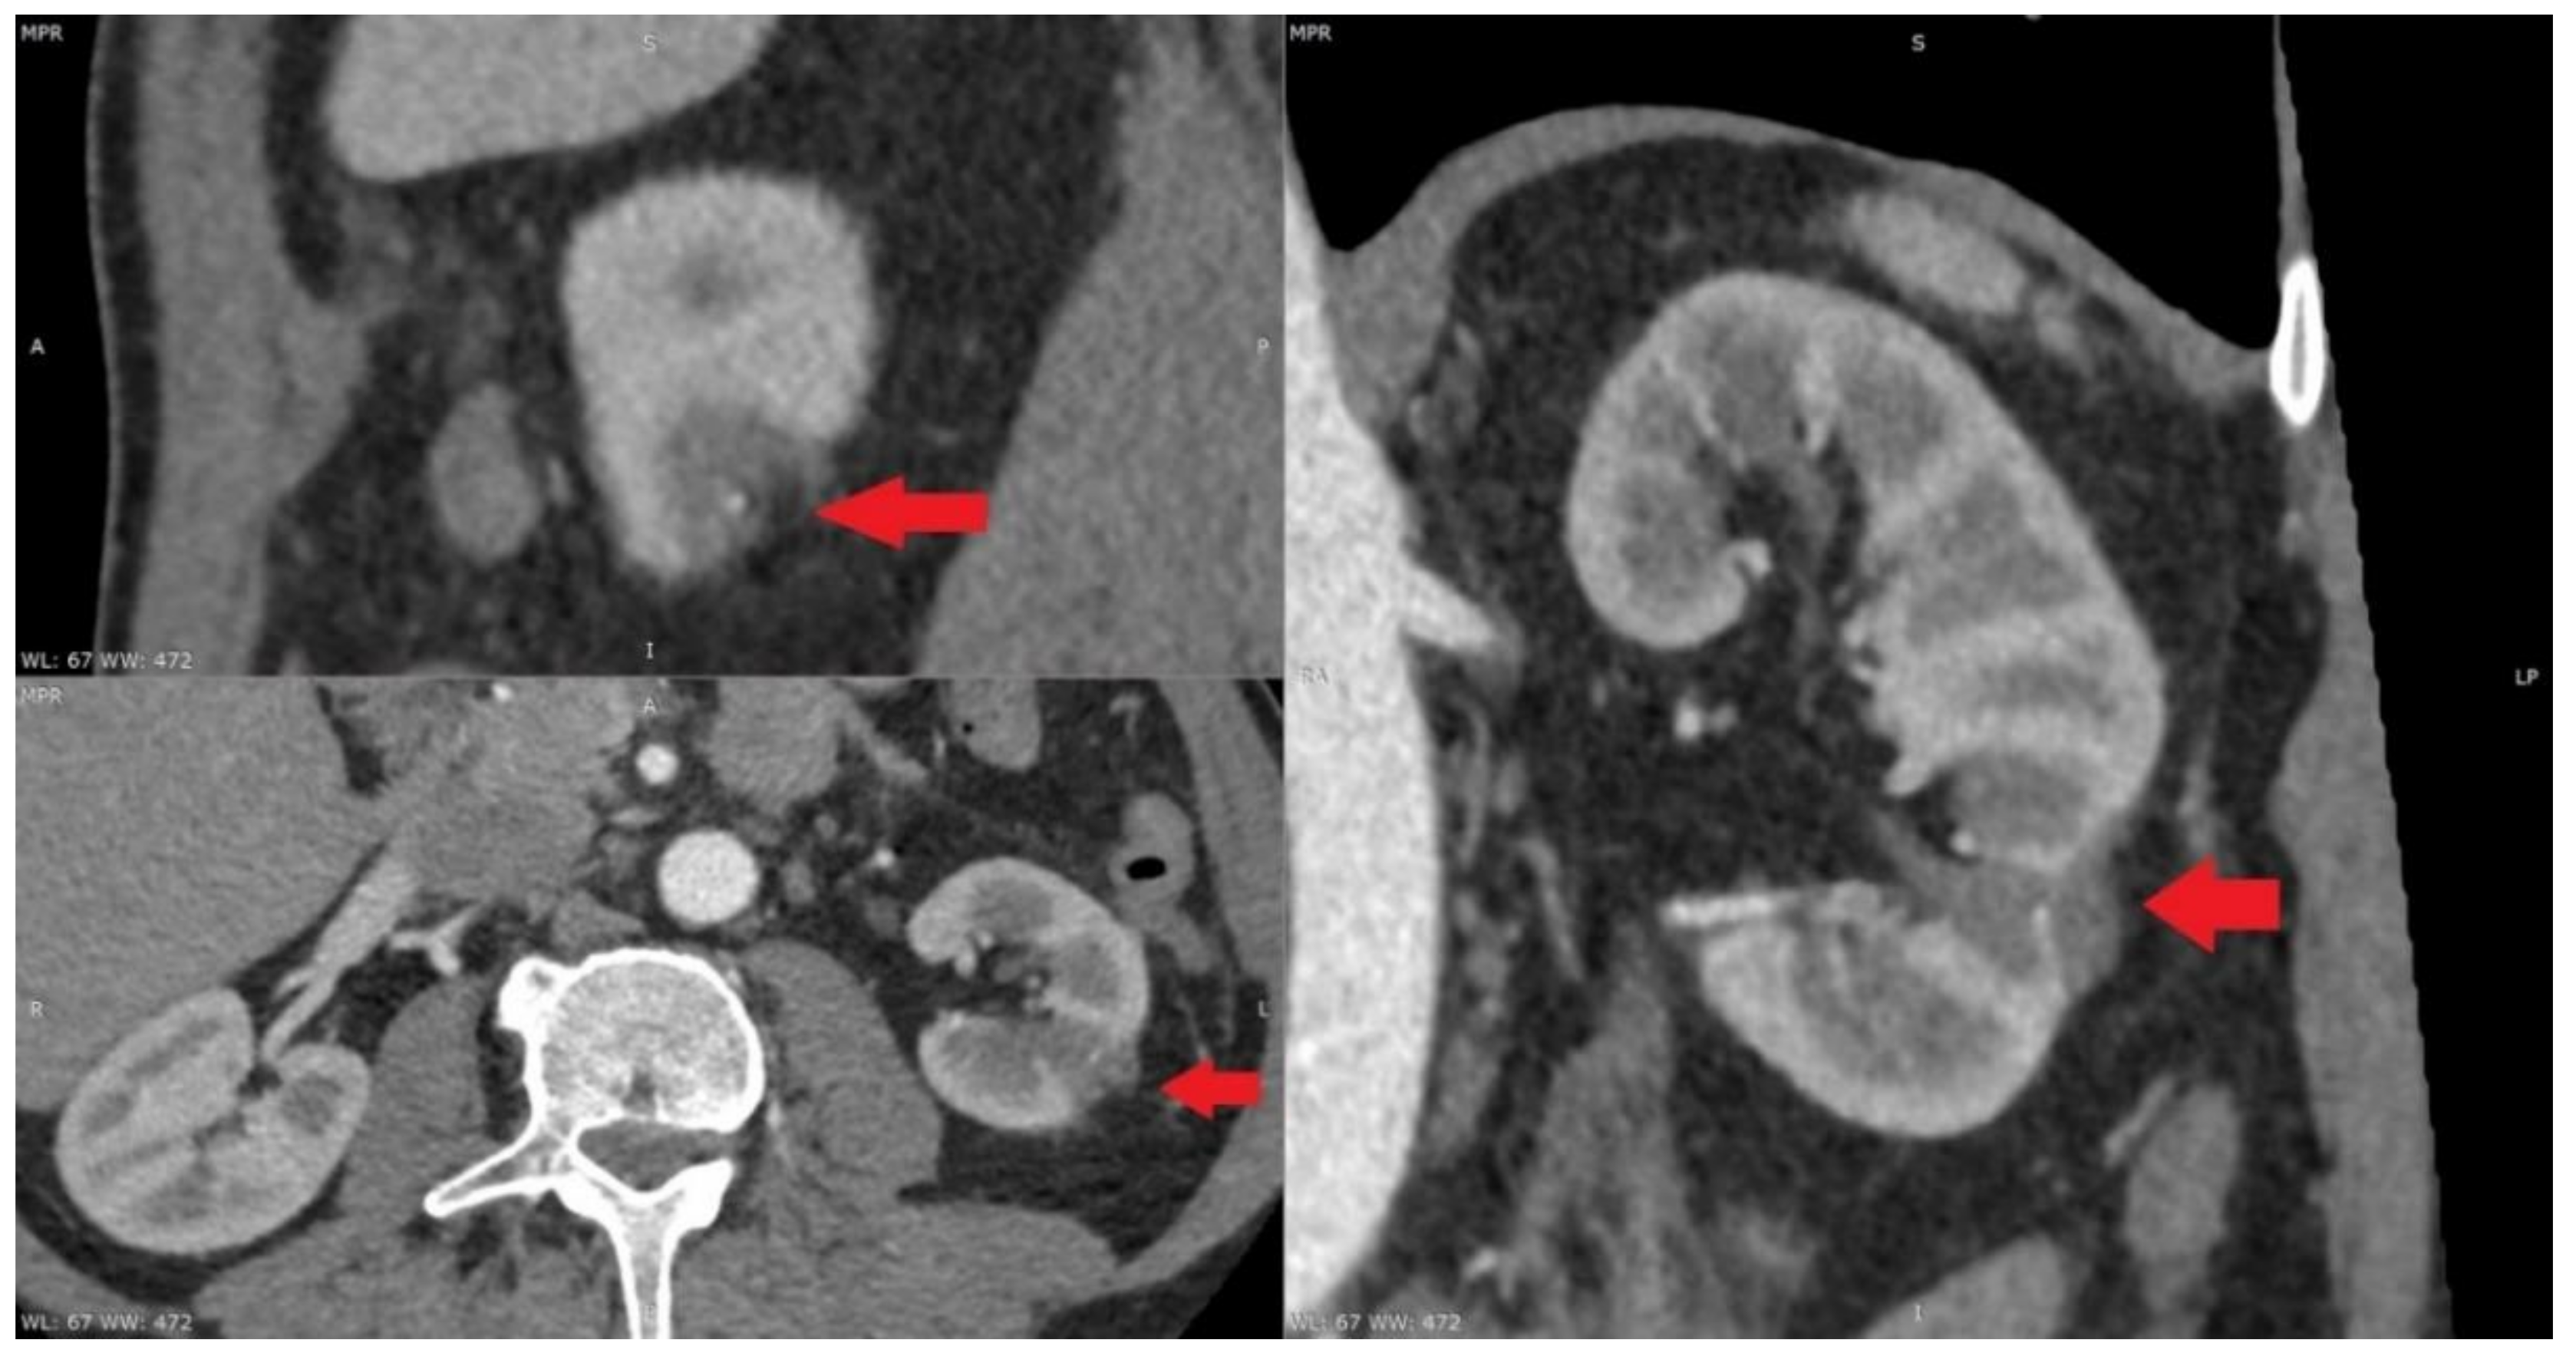

At present, the most widely used thermal ablative techniques are microwave ablation, radiofrequency ablation and cryoablation. The indications for MWT were considered to be comorbidity, patients’ desire for minimally invasive treatment, age, hereditary disease, solitary kidney and decreased renal function. For elderly patients, comorbid patients and patients with hereditary kidney tumors, MWT is an effective treatment modality. Microwave thermal ablation has become a viable option for the treatment of small kidney tumors (Figure 1). MWT ablation is a less invasive, less morbid treatment option (Figure 2). Microwave thermal ablation offers many benefits of other ablation techniques and offers several other advantages (faster ablation times, the ability to use multiple applicators simultaneously, higher intratumoral temperatures, less procedural pain). Excellent cancer management with rigorous follow-up periods has been reported previously in hospitals with a high volume of MWT [5,6,7]. Recently, in a retrospective review of 29 consecutive patients with a total of 30 RCC (23 T1a; 7 T1b), a technical success was achieved for 22 T1a (96%) and 7 T1b (100%) tumors using a third-generation system [8]. The present clinical study is the first to compare MWT with OPN in the treatment of elderly patients as radical surgery was often associated with an increased risk of operative and postoperative complications. Patients in MWT group were older in age. Furthermore, patients in MWT group had more comorbidities than patients undergoing open kidney resection. This study is also the first attempt to rate the pain level following the surgery. The data points to the fact that MWT treatment patients complained of less pain, thus indicating that MWT treatment is more comfortable for patients after the procedure and reduces the need for analgesics. The present study shows that MWT is an effective method for treating elderly patients with multiple comorbidities. Tumor size, RENAL nefrometry score and localization did not differ between the two analyzed groups. In our study, MWT procedure was ineffective for only 1 (6.66%) patient. This patient underwent repeated MWT. After 1 month, contrast was no longer accumulated in the tumor in control CT. Percutaneous MWT appeared to be beneficial for the majority of the patients in the present study. There was no relapse during the monitoring period. After follow-up, no distant metastases were detected. Overall survival rate was 100% (Figure 3). This suggests that MWT is an effective treatment method for T1a renal tumors. Another important aspect for older patients with multiple comorbidities is glomerular filtration rate (eGFR). Many studies have shown that chronic renal failure is associated with worse patient prognosis. All patients with stage 3 chronic kidney disease have a higher mortality and cardiovascular risk, compared with patients without chronic kidney disease. Kidney function is the main criteria for patient survival. Keeping kidney function is important because the prevalence of chronic kidney disease is estimated to be 46.8% in those older than 70 years [9]. Keeping kidney function is particularly important because renal insufficiency in older people is a strong and independent predictor of mortality. The significant correlation between predicted GFR and mortality persisted after adjustment for the effects of numerous common risk factors, including gender, smoking, hypertension, diabetes, serum cholesterol level, ischemic heart and cerebrovascular disease, BMI and physical activity [10]. In our study, baseline eGFR was lower in OPN group and its reduction after renal resection was not as dramatic as we expected. In our study, we can see that the difference in eGFR before and after MWT and OPN is reduced, but that difference is not statistically significant. Post-hoc power statistical analysis showed that the eGFR in the microwave thermal ablation group may be 13.8% lower. All patients after surgery had stage 3 kidney disease. It is expected that after minimally invasive treatment, MWT will damage kidney parenchyma less and preserve renal function. Unfortunately, our study showed that the estimated glomerular filtration rate was not better after MWT when compared with OPN. However, this may be due to the small number of patients in the study. Patients before MWT had a lower HGB. This may be related to other comorbidities. However, the difference between the groups before and after surgery was not statistically significant. Using post-hoc statistical analysis, we found a 59.6% reduction in HGB in patients after OPN. What is more interesting is that the greater half of patients who underwent MWT were at a higher risk for surgery, but the complication rate was lower and the oncological outcome was reasonable. In MWT group, patients’ ASA was worse than in OPN group, but it was not statistically significant. This shows that MWT is a suitable and safe treatment method for patients who have severe comorbidities, and for who general anesthesia and standard surgery are contraindicated. Our study concluded that patients with small kidney tumors, similar tumor location, RENAL nefrometry score and size had shorter operation times, felt less pain and shorter hospitalization times after MWT than OPN. Nevertheless, the results of this study demonstrated that MWT is superior to OPN in terms of patients’ general condition and serious comorbidities. Tumor size or location did not have any impact on changes in renal function. Though minimally invasive treatment options are determined by anatomical features (kidney tumor on the anterior surface of the kidney, tumor near to the intestine or tumor near the large renal vasculature or kidney collector) and insufficient long-term monitoring data, they are effective in kidney cancer treatment, especially for elderly patients with comorbidities. However, the present study has some limitations that warrant discussion. First, our study is a retrospective study, introducing the potential for selection bias and additional confounders. Second, there are many other MWT devices used by hospitals. Therefore, our outcomes may not be applicable universally and a more in-depth inclusive study is required.

Figure 1.

Tumor in the lower left renal pole (15 × 15 × 20 mm) before microwave thermal ablation.